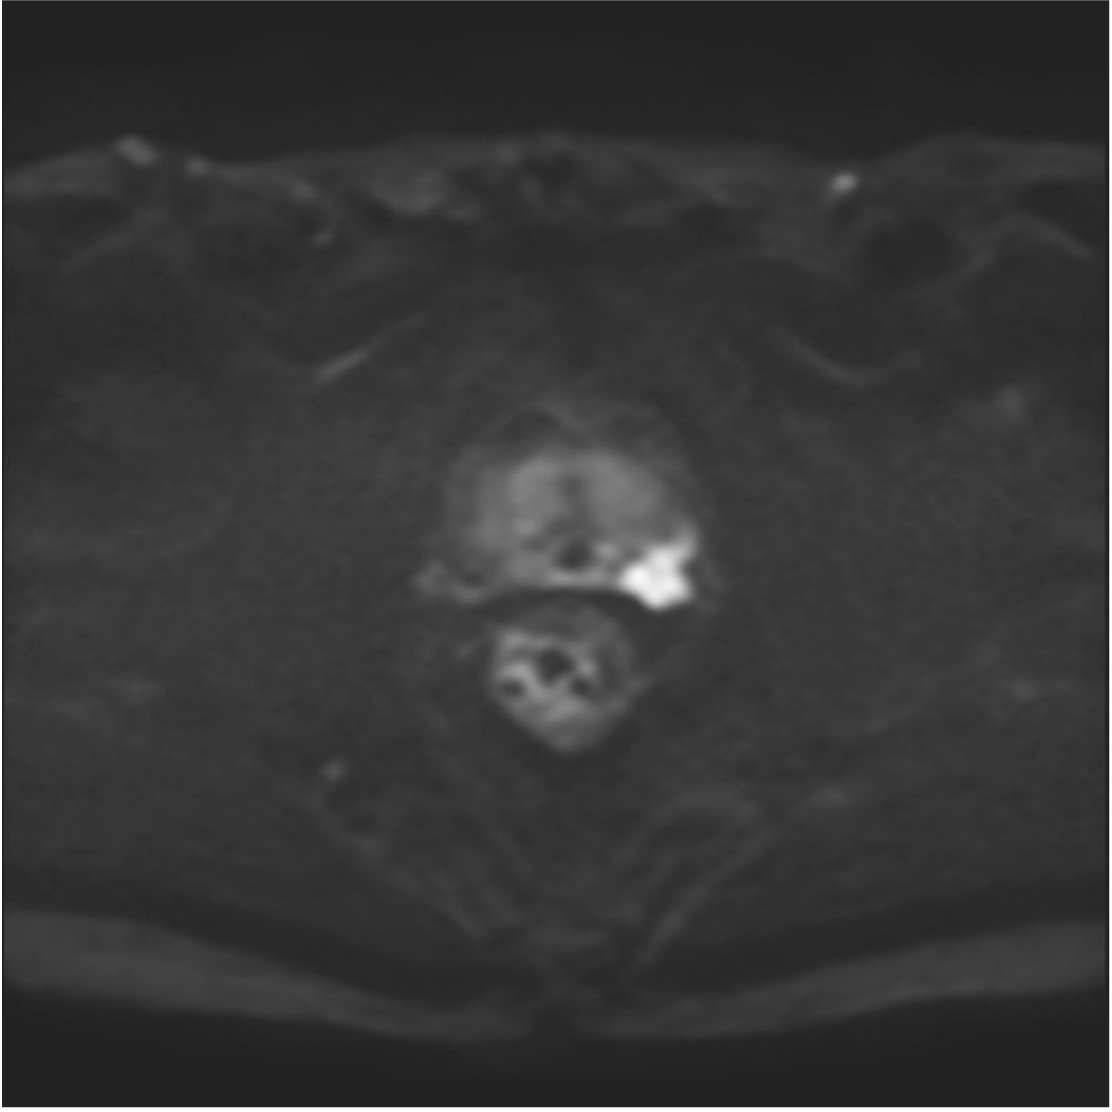

当院では、2008年から前立腺針生検前にはMRI(造影剤を使わない単純撮影)を行っております。これまでに当院放射線科では、2000例以上の前立腺MRI検査実施経験から、細かい撮影条件設定を行い、よりS/N比の高い画像を得るための努力を続けてきております。下に示す画像(Fig.1)は、最近の3T-MRIでの代表的前立腺癌症例ですが、前立腺左葉辺縁域にはっきりと撮影されている癌病巣がわかると思います。PSA二次検診の方法には施設によってさまざまですが、現在では前立腺癌診断には、このMRIで得られる画像所見こそが、最も客観的かつ診断に寄与する、と考えております。当院の画像をぜひご覧ください。

現在まで、当院のPSA二次検診では、できるだけお待たせしないように3T・MRI検査を実施し、癌が想定される部位をあらかじめ確認して、その所見部位を正確に生検するという、標的生検法を行っております(経会陰式)。こうした画像をもとに前立腺生検を行うとすれば、例えば1本でも正確に採取できれば癌診断ができると考えております(実際には標的部位本数+6本程度)。二次検診MRIで癌を疑う所見がないとすれば、前立腺肥大症か前立腺炎と考えられますので、排尿症状などに応じて適切に内服治療し、経過観察ができれば、迅速な針生検検査は避けてよい、と考えています。

Fig.1 MRI